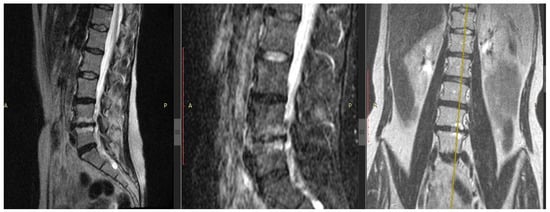

Localization of IVD hernia in 23.53% (n = 8) of individuals was at the level of L4/5, in 76.47% (n = 26)—at L5/S1. The average value of the IVD height demonstrated a significant narrowing of the intervertebral space at the level of the operated disc (L4/5, L5/S1) compared to the L3/4 level—the average values of the IVD height were 0.86 ± 0.16 and 2.61 ± 0.15 mm, respectively (p < 0.01). The stage of IVD degeneration at the discectomy level according to Pfirrmann corresponded to the 4th and 5th stages in 55.88% (n = 19) and 38.24% (n = 13), respectively. In half of the patients (n = 19; 55.88%), reactive changes in the adjacent vertebrae bodies were detected: the bone marrow edema (Modic-1) in 26.47% (9 patients) and fatty degeneration of the bone marrow (Modic-2) in 29.41% (10 patients) (see Figure 1). Almost half of the patients in the DDD group (n = 16; 47.06%) had a combination of IVD hernia plus Modic changes with EP erosive lesion of the adjacent vertebral bodies.

Figure 1.

Patient with back pain. Magnetic resonance imaging of the lumbar spine, modes T2-weighted images with fat suppression in sagittal sections (left and center images, respectively), T2-weighted short-tau inversion-recovery image in the coronary section (right image). Right-sided lumbar scoliosis, the 5th stage of degenerative disc disease by Pfirrmann at the L4/5 and 4th stage—at the L5/S1 level, with IVD hernias L4/5 and L5/S1, erosion of the endplates and Modic changes type 1 in the vertebral bodies L4/5 (yellow axis carried out via Modic-1). Modic-1 = the bone marrow edema; Modic-2 = the bone marrow fatty degeneration.